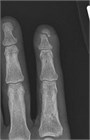

Tuft fractures often result from a crush injury to the distal tip of a finger. Closed tuft fractures can be managed with analgesia alone. A digital block and drainage of a subungual hematoma can be considered for pain control. Open tuft fractures require exploration and extensive irrigation after analgesia (often with a digital block). The nail bed should be sutured to cover exposed bone. Local wound care is the best strategy to prevent an infection, but if there is gross contamination, a short course of antibiotics can be considered. Typically, these fractures do not require splinting.